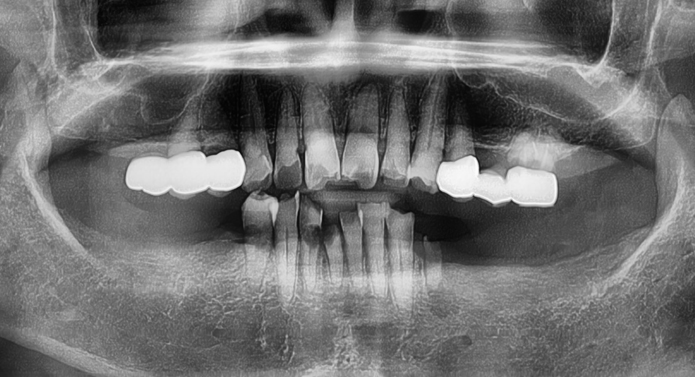

문제가 생긴 보철물(크라운·브릿지 등)만 정밀하게 제거하고

새롭게 제작·장착하는 고난도 치료입니다.

단순한 탈락이나 파절이 아닌 교합력 문제,

지대주 헐거움, 잇몸 염증 등

다양한 원인을 정확히 분석하고 교정하는 것이 핵심입니다.

※ 결국 임플란트를 다시 심어야 하는 상황까지 발생할 수 있습니다.